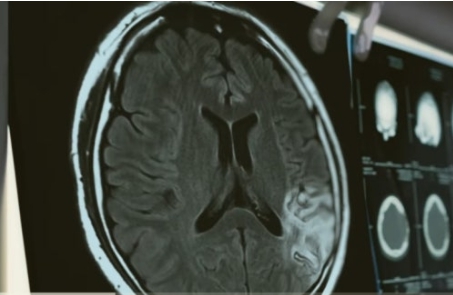

뇌졸중(뇌경색, 뇌출혈) 검사

심뇌혈관 질환의 조기발견과 예방을 위해 40~50대이거나, 흡연, 고혈압, 당뇨, 심장 질환의 가족력 등 심뇌혈관 질환의 고위험군이라면 뇌 MRI, 뇌 MRA, 경동맥 초음파, 경동맥 MRA를 통해 뇌혈관 혈류의 속도, 상태 등을 점검하고 필요에 따라 적절한 시술을 받는 것이 좋습니다.